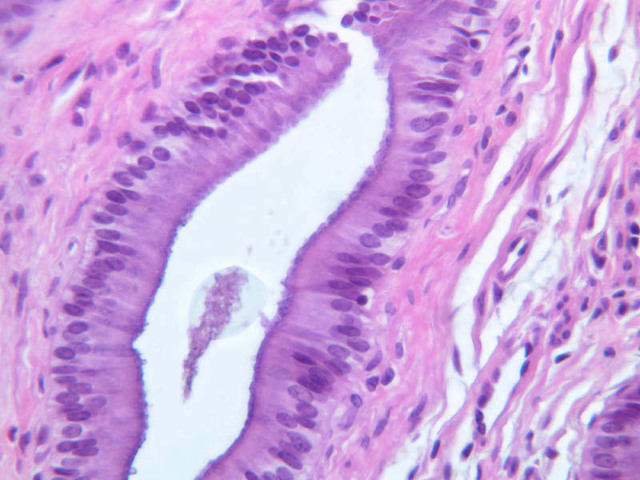

Sections through the wall of the gall bladder appear on slide B-33 (H&E [2.5x, 10x, 20x-labeled, 40x-labeled] [2.5x, 10x, 20x, 40x]). As you examine the epithelium, try to identify the striated border, which functions in absorbing water from the bile. Look for lymphocytes, capillaries and small mucous glands in the lamina propria; lymphocytes often appear to invade the epithelium itself. The gallbladder does not have a discernible submucosa; rather, a muscularis layer, consisting of smooth muscle and connective tissue underlies the mucosa. Some sections may permit identification of both a tunica adventitia, which binds the gallbladder to the liver, and a tunica serosa where the gallbladder faces the peritoneal cavity.

4 Columnar Epithelium Ep H&E b33 gallbladder 40x labeled.jpgB33, Gallbladder, 40x

5 Striated Border SB H&E b33 gallbladder 40x labeled.jpgB33, Gallbladder, 40x

6 Lymphocytes L H&E b33 gallbladder 40x labeled.jpgB33, Gallbladder, 40x